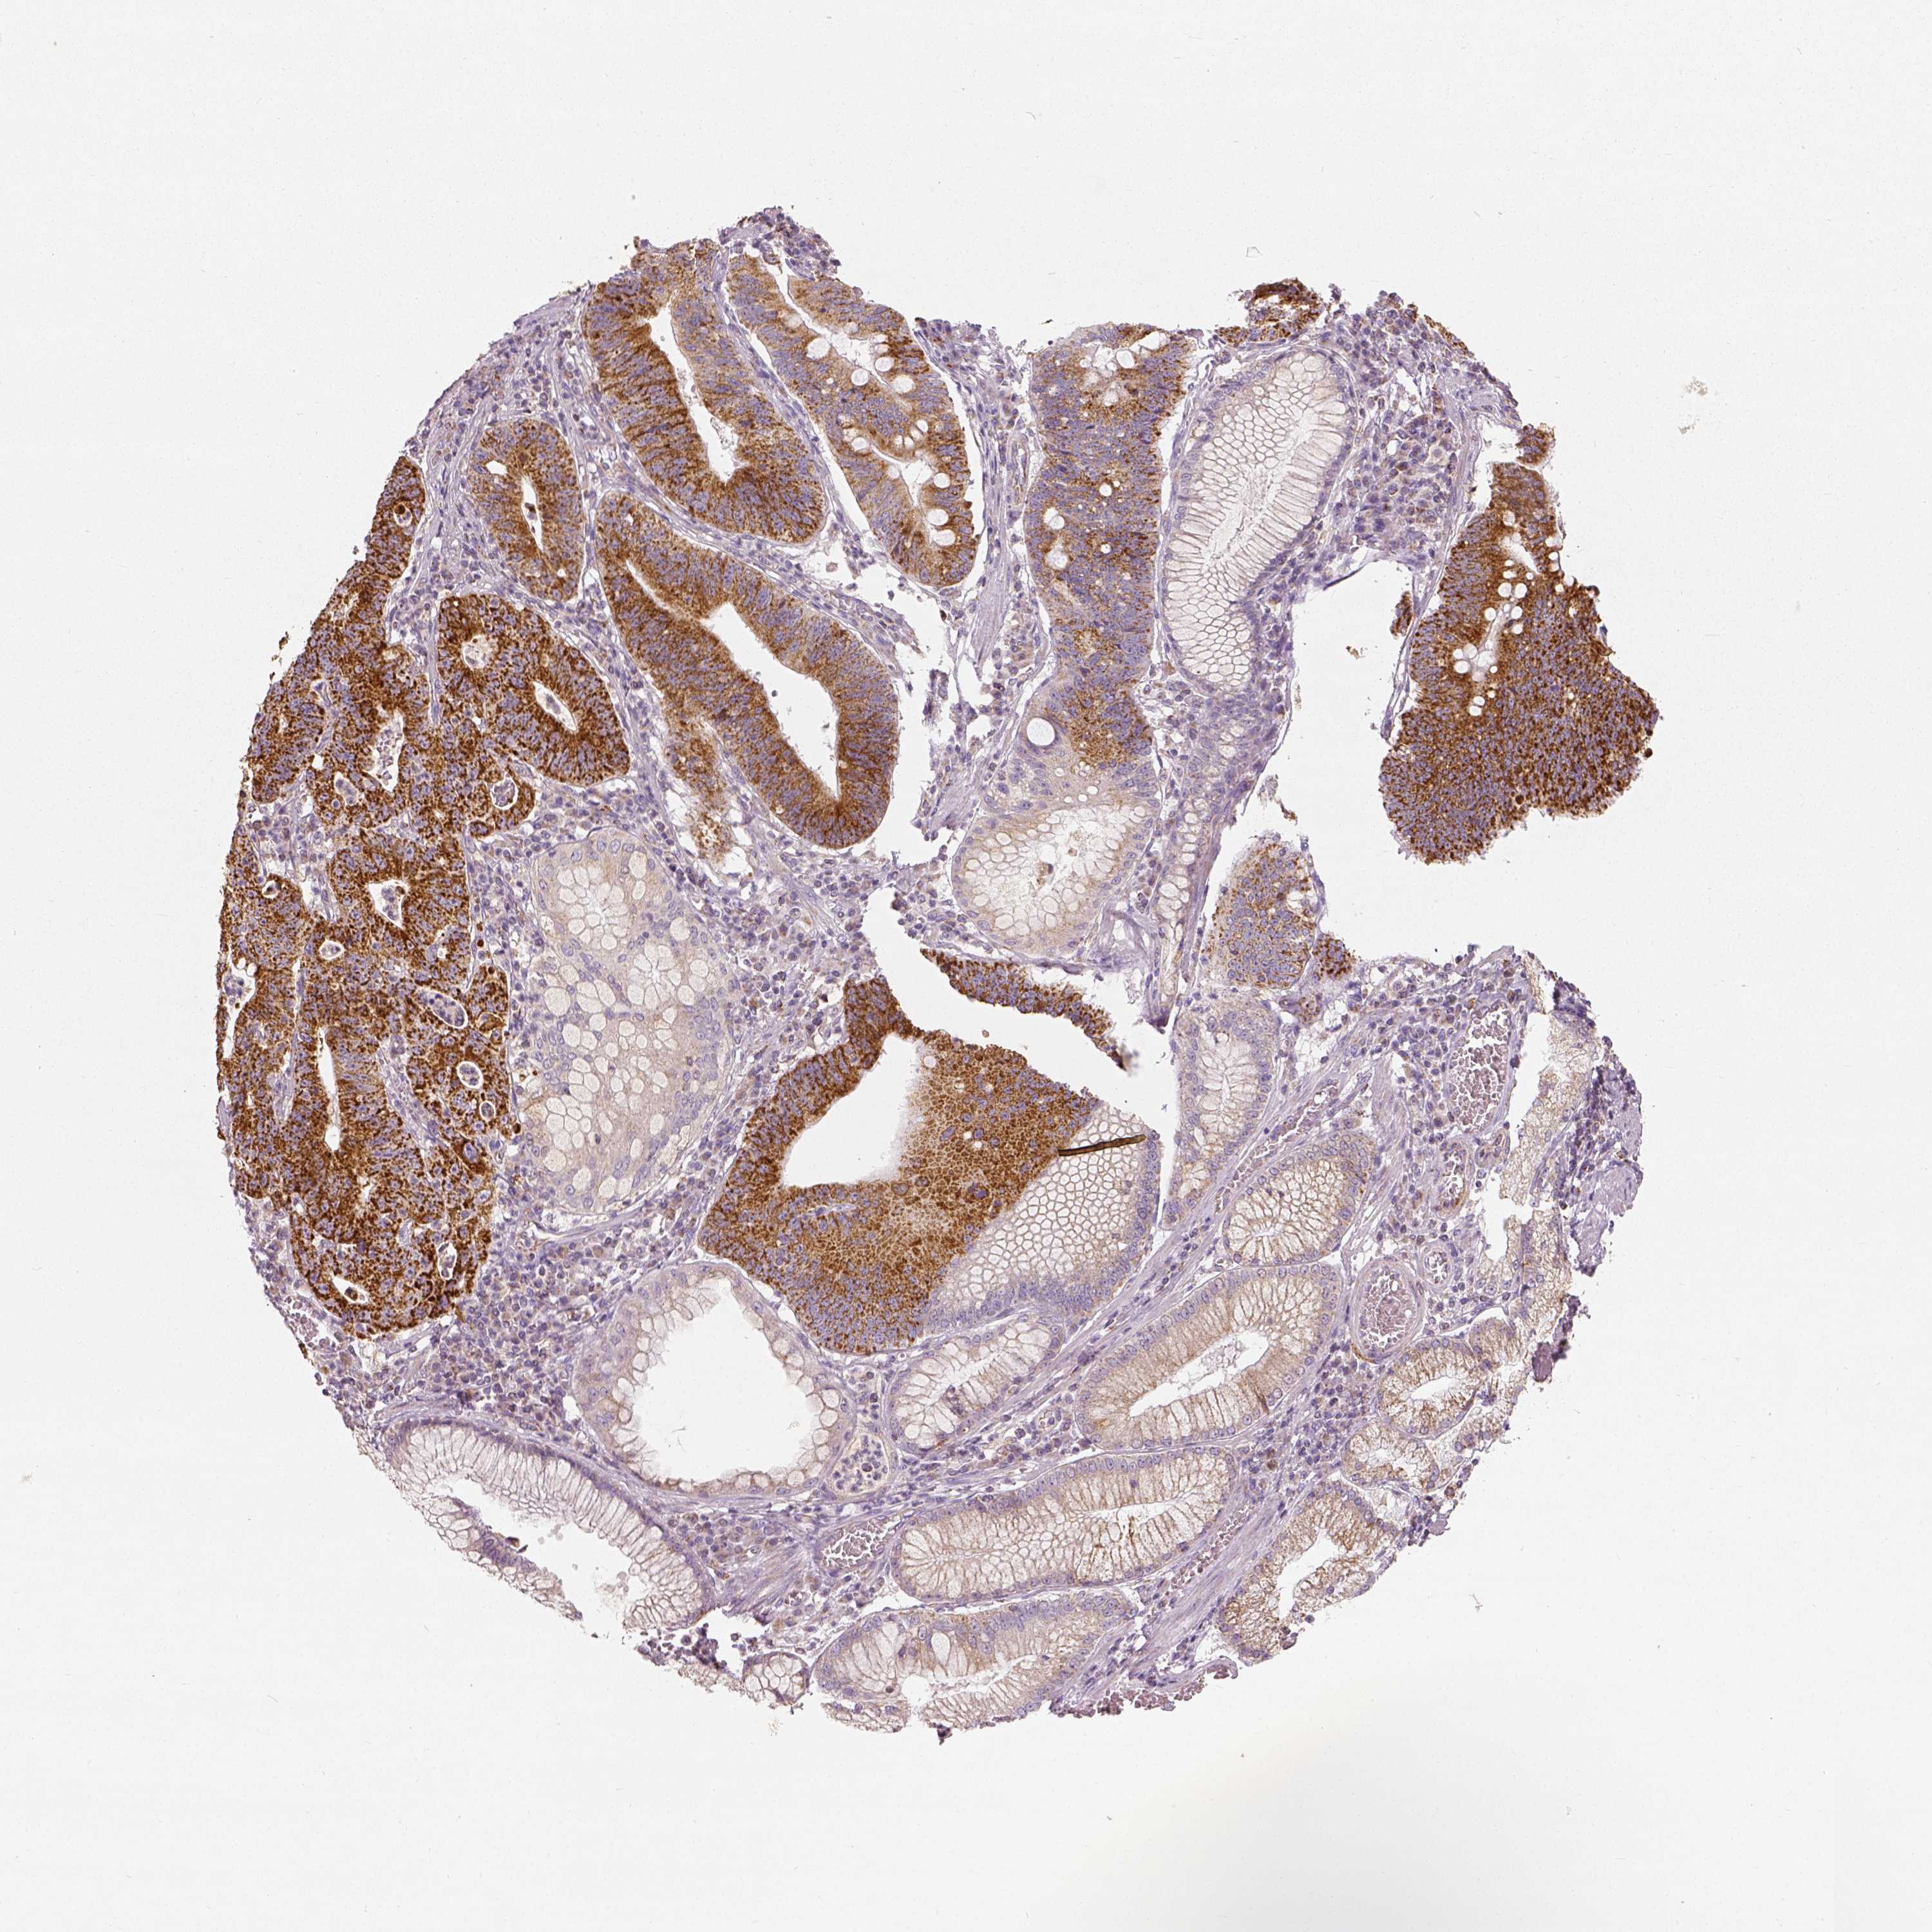

STOMACH CANCER - Protein expressioni

A mouse-over function shows sample information and annotation data. Click on an image to view it in a full screen mode. Samples can be filtered based on level of antibody staining by selecting one or several of the following categories: high, medium, low and not detected. The assay and annotation is described here.

Note that samples used for immunohistochemistry by the Human Protein Atlas do not correspond to samples in the TCGA dataset.

Antibody stainingi

Antibody staining in the annotated cell types in the current human tissue is reported as not detected, low, medium, or high, based on conventional immunohistochemistry profiling in selected tissues. This score is based on the combination of the staining intensity and fraction of stained cells.

Each image is clickable and will lead to virtual microscopy that enables deeper exploration of all samples and also displays staining intensity scores, fraction scores and subcellular localization as well as patient and tissue information for each sample.

Antibody HPA036978

Antibody HPA036979

Antibody CAB068215

Staining

High

Medium

Low

Not detected

Intensity

Strong

Moderate

Weak

Negative

Quantity

>75%

75%-25%

<25%

None

Location

Nuclear

Cytoplasmic/membranous

Cytoplasmic/membranous,nuclear

Adenocarcinoma, NOS